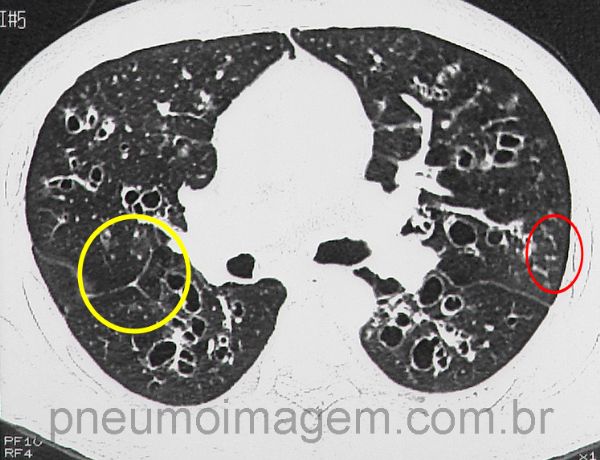

Aspergilose Broncopulmonar Alérgica (ABPA). Bronquiectasias centrais e impactação de muco (setas amarelas). Na ABPA há eosinofilia (>500/mm³), IgE muito elevada (>1000 UI/ml), IgG anti-Aspergillus e IgE específica (RAST) contra Aspergillus também elevadas. A ABPA faz parte do diagnóstico diferencial da asma de difícil controle.

Além das bronquiectasias centrais e impactação de muco, pode-se observar perfusão em mosaico (amarelo), indicando aprisionamento aéreo, e nódulos centrolobulares (vermelho).

Chaves: árvore em brotamento; árvore em florescência; tree in bud; bronchopulmonary allergic aspergillosis; bronchiectasis; centrolobular nodules (red); mosaic perfusion (yellow).